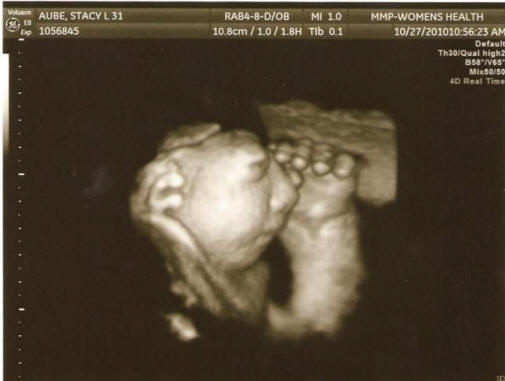

Valokuvia avoimista lähteistä asiantuntijat pitivät raskaana olevien naisten sairauskertomuksia 27: stä synnytyssairaaloilla rekisteröidyt alueet, tutkitaan missä he työskentelivät kuin olivat sairaita, juoivatko he alkoholia, huumeita tai savustettuja tuotteita, millä alueella he asuivat ja mistä lähde joi vettä. Loppujen lopuksi hallituksen virkamiehet totesivat, että he eivät pystyneet selvittämään ehtoja tai syitä tästä ilmiöstä. “Tulokset olivat pettymys, mutta ei aivan odottamaton, osallistui osallistunut tutkija Jim Kucik (Jim Kucik) tutkimuksessa. – Yleensä sellaiset synnynnäiset viat aiheuttavat tekijöiden yhdistelmä, jota on erittäin vaikea havaita. ei on mahdollista, että kaikki tämä on vain sattumaa. ” Ja tässä on geneettinen konsultti Susie Ball uskoo, että kolmessa maakunnassa Washingtonin osavaltiossa on joitain ongelmia, jotka pitäisi antaa tarkempi huomio naisten suojelemiseksi tulevaisuudessa hedelmällisessä iässä. Varo, järkyttävä valokuva.

Valokuvia avoimista lähteistä